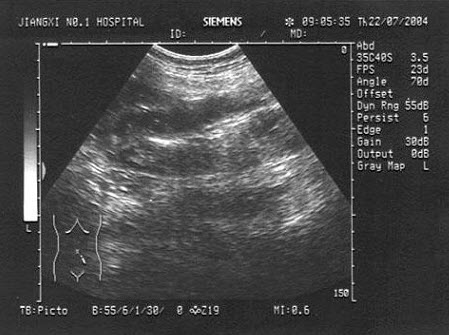

92、单项选择题

该病例最有可能诊断是()

A.布-加综合征

B.川崎病

C.动脉瘤

D.以上都不是

E.门静脉高压